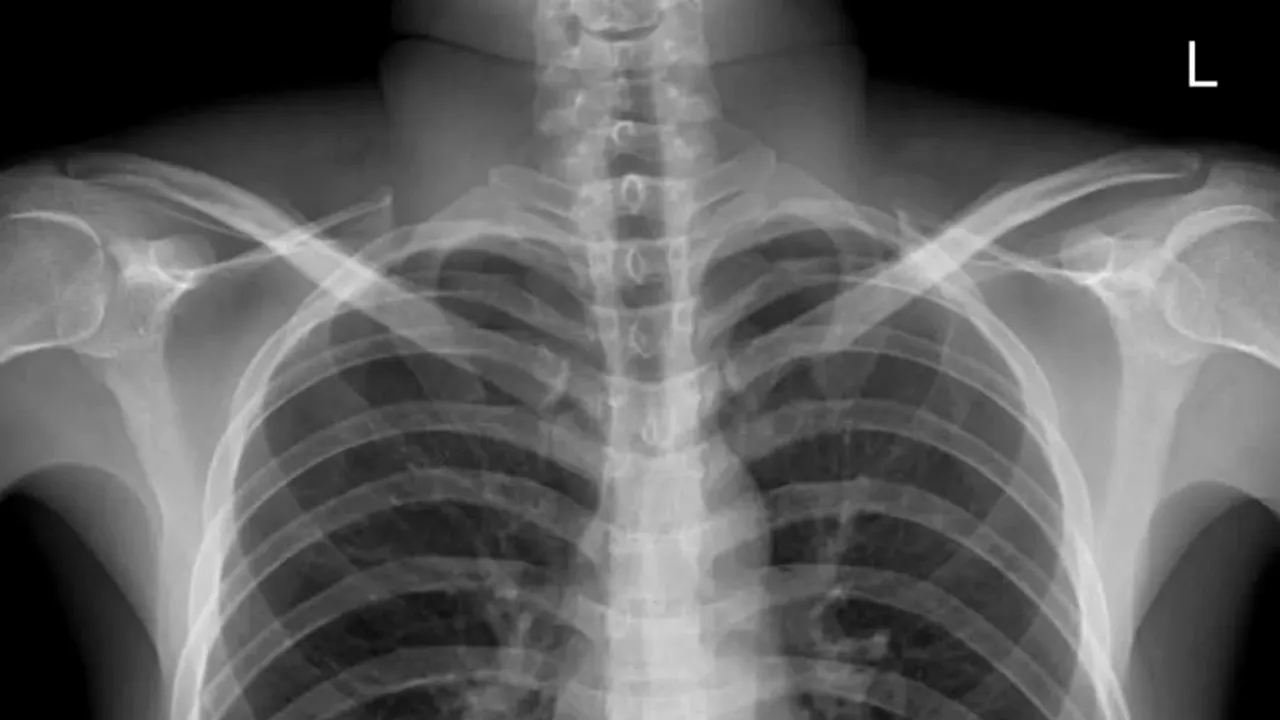

După ce doctorii i-au făcut o radiografie, au fost șocați să vadă că acele chei, pierdute cu o seară în urmă, îi erau blocate la nivelul esofagului. Însă, se pare că și bărbatul a fost la fel de surprins precum doctorii, potrivit site-ului Soho, și nu avea idee cum ajunseseră cheile acolo.

Doctorii au analizat toate variantele pentru a-l ajuta pe Chang să scape de durere, dar cea mai bună a fost operația de urgență.

Doctorul Zhang Yuyu  a spus reporterilor că extragerea cheilor a fost destul de dificilă. După ce i s-a adnistrat anestezia, un gastrointerelog a reușit să îi scoată cheile, dar și cardul pentru interfon, din esofagul bărbatului.